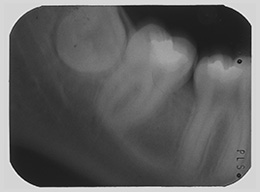

Dieser Zahn wurde schon geraume Zeit zuvor von einer Kollegin im Notdienst eröffnet und anschlies­send mit einer aufwendigen Amal­gamrestauration ästhetisch an­sprechend wieder verschlossen. (Bild 1) Uns blieb noch WK/WF, was bei massiver Überstopfung der hin­teren Wurzel auch gelang (Bild 2).

"Überstopfen ist immer noch besser als Unterstopfen" laut Koçkapan. OK, hier wurde des Guten aber ganz eindeutig zuviel getan.

Also direkt neben dem Zahn das Zahnfleisch ein wenig angehoben und zur Seite gedrängt und dann mit einem scharfen Löffel den Überschuss vollständig entfernt.

Schon 8 Monate später ist eine deutliche Verbesserung der Gesamt­situation unverkennbar (Bild 3). Verlorengegangene Knochensubstanz wurde in Teilen schon wieder aufge­baut, doch ist noch gar nichts entschieden. Schaun mer also ma'.

Abrechnungstechnisch hat der Mut zur WR an 38 gefehlt, deshalb nur EXZ1.